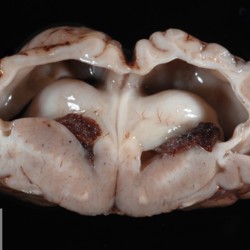

Pàgina anterior de 637 Pàgina següent 3181 total Bovine Specie: Bovine Organ: Bone Lesion: Osteomyelitis Lesion modifier: Osteomyelitis - Purulent Disease: - Position: 136 (2 views) Bovine Specie: Bovine Organ: Brain Lesion: Hydrocephalus Lesion modifier: - Disease: Schmallenberg Files/Expedient: N-84/13 Position: 253 (1 views) Bovine Specie: Bovine Organ: Brain Lesion: Hydrocephalus Lesion modifier: - Disease: Schmallenberg Files/Expedient: N-84/13 Not viewed Bovine Specie: Bovine Organ: - Lesion: Hypoplasia Lesion modifier: - Disease: Schmallenberg Files/Expedient: N-84/13 Not viewed Bovine Specie: Bovine Organ: Fetus Lesion: Arthrogryposis Lesion modifier: - Disease: Schmallenberg Files/Expedient: N-84/13 Position: 253 (1 views) Pàgina anterior de 637 Pàgina següent Títol Select...Avian (Exotic) (110)Avian (Poultry) (76)Bovine (317)Canine (935)Caprine (47)Equine (257)Feline (326)Ferret (19)General (127)Marine mammal (22)Non-human primate (20)Ovine (328)Porcine (379)Rabbit (61)Reptile (38)Rodent (28)Wildlife (91) Format Select...- (60)Abomasum (37)Adrenal gland (10)Blood (7)Blood vessel (50)Body as a whole (19)Bone (57)Bone marrow (21)Brain (93)Cloaca (1)Diaphragm (2)Ear (5)Esophagus (39)Eye (16)Fetus (12)Gallbladder (23)Gizzard (2)Heart (265)Intestine (356)Joint (32)Kidney (443)Larynx (5)Liver (326)Lung (264)Lymph node (91)Mammary gland (10)Mediastinum (1)Muscle (22)Nasal cavity (22)Nerve (7)Omasum (5)Oral cavity (63)Ovary (14)Oviduct (8)Pancreas (7)Parathyroid (5)Penis (10)Peritoneum (65)Pharynx (9)Pituitary gland (6)Placenta (7)Prostate (8)Proventriculus (3)Reticulum (1)Rumen (28)Sinus (7)Skin (181)Spinal cord (15)Spleen (105)Stomach (125)Teeth (1)Testicle (11)Thoracic cavity (31)Thymus (13)Thyroid gland (5)Tongue (32)Tonsils (11)Trachea (11)Urethra (5)Urinay bladder (61)Uterus (27)Vagina (1)Vulva (1)Yolk sac (1) Cobertura Select...- (152)Abomasitis (26)Abscess (27)Acidosis (1)Adenocarcinoma (20)Adenoma (9)Aerosacculitis (6)Agenesis (1)Agnathia (1)Alopecia (7)Amyloidosis (12)Aneurysm (6)Angiectasis (1)Anthracosis (1)Arteritis (11)Arthritis (15)Arthrogryposis (6)Artifact (4)Ascites (13)Atelectasis (8)Atherosclerosis (5)Atresia (1)Atrial septal defect (2)Atrophy (10)Autolysis (7)Bronchitis (6)Bronchopneumonia (26)Cachexia (2)Carcinoma (103)Cardiomyopathy (19)Cellulitis (2)Chemodectoma (4)Cholangiohepatitis (4)Cholangitis (19)Cholecystitis (4)Cholestasis (5)Chondrodysplasia (2)Chondrosarcoma (2)Chronic passive congestion (13)Chylothorax (2)Cirrhosis (6)Coelomitis (3)Coenurus cerebralis (4)Colitis (40)Congestion (17)Conjunctivitis (5)Coronitis (3)Cryptorchidism (3)Cyst (25)Cystitis (24)Dermatitis (69)Diaphragmatic hernia (4)Dilation (28)Discospondylitis (1)Disseminated intravascular coagulation (7)Dyschondroplasia (1)Dysplasia (29)Ectopia cordis (1)Ectopic ureter (1)Edema (55)Emphysema (5)Encephalitis (5)Endocardiosis (14)Endocarditis (26)Endometritis (5)Enteritis (118)Enterolith (6)Epulis (3)Esophagitis (14)Fasciitis (1)Fibrosis (7)Fibrous osteodystrophy (8)Fistula (1)Folliculitis (3)Fracture (2)Gastritis (34)Gingivitis (5)Glioma (8)Glomerulonephritis (21)Glossitis (25)Glycogenosis (1)Gout (8)Granuloma (2)Granulosa cell tumor (4)Hemangioma (9)Hemangiosarcoma (46)Hematoma (8)Hemoglobinuria (2)Hemopericardium (12)Hemoperitoneum (2)Hemorrhage (100)Hemosiderosis (7)Hemothorax (2)Hepatitis (78)Hernia (11)Histiocytosis (3)Hydatid cyst (11)Hydrocephalus (9)Hydrometra (1)Hydronephrosis (22)Hydropericardium (6)Hydrothorax (3)Hydroureter (5)Hyperkeratosis (8)Hyperostosis (4)Hyperplasia (37)Hypertrophy (9)Hypopigmentation (1)Hypoplasia (7)Hypopyon (1)Impaction (6)Infarction (63)Insulinoma (6)Intussusception (5)Jaundice (17)Laminitis (2)Laryngitis (2)Leiomyoma (5)Leukemia (13)Lipidosis (36)Lipoma (7)Lymphadenitis (45)Lymphadenopathy (7)Lymphangiectasia (6)Lymphangitis (5)Lymphoma (221)Malacia (11)Malignant melanoma (15)Mast cell tumor (11)Mastitis (8)Megaesophagus (2)Melanosis (3)Melena (4)Meningioma (6)Meningitis (6)Meningocele (2)Meningoencephalitis (5)Mesothelioma (5)Methemoglobinemia (2)Mineralization (10)Mucocele (5)Mucometra (1)Multilobular bone tumor (1)Mummification (3)Myelofibrosis (1)Myocarditis (4)Myositis (5)Necrosis (81)Nephritis (113)Nephroblastoma (6)Nephrosclerosis (1)Nephrosis (14)Neuritis (1)Obstruction (13)Omasitis (4)Omphalitis (1)Omphalophlebitis (7)Orchitis (4)Osteoarthrosis (5)Osteomyelitis (9)Otitis (2)Palatoschisis (3)Pancreatitis (3)Panniculitis (3)Papilloma (7)Parakeratosis (14)Patent ductus arteriosus (6)Peliosis hepatis (1)Perforation (17)Pericarditis (35)Peritonitis (39)Persistent right aortic arch (1)Pharyngitis (2)Pheochromocytoma (2)Phlebitis (2)Placentitis (6)Pleuritis (21)Pleuropneumonia (24)Pneumonia (109)Pneumothorax (3)Polycystosis (14)Polyp (5)Polyserositis (6)Posthitis (1)Proctitis (4)Prolapse (3)Prostatitis (3)Proventriculitis (1)Pyelonephritis (24)Pyometra (6)Pyothorax (4)Rhinitis (11)Rumenitis (6)Rupture (24)Salpingitis (3)Sarcoma (57)Sclerosis (1)Scoliosis (2)Seminoma (2)Sequestrum (2)Serous atrophy (14)Sinusitis (7)Splenitis (14)Splenomegaly (9)Spondylitis (6)Spondylosis (1)Stenosis (9)Stomatitis (32)Tenosynovitis (2)Teratoma (3)Thricobezoar (2)Thrombosis (16)Tonsilitis (4)Torsion (13)Tracheitis (4)Tympany (7)Typhlitis (8)Typhlocolitis (4)Ulcer (43)Urethritis (1)Urolithiasis (36)Uroperitoneum (1)Uveitis (1)Vasculitis (15)Ventricular septal defect (3)Volvulus (11) Matèria Select... - (14)- (1653)- (152)Abomasitis - Catarrhal (2)Abomasitis - Catarrhal-hemorrhagic (1)Abomasitis - Chronic (1)Abomasitis - Fibrinous-necrotizing (2)Abomasitis - Hyperplasic (5)Abomasitis - Hyperplasic - Chronic (1)Abomasitis - Necrotic (1)Abomasitis - Necrotizing (2)Abomasitis - Ulcerative (5)Adenocarcinoma (9)Aerosacculitis - Granulomatous (1)Amyloidosis - Chronic (1)Arteritis - Necrotic (2)Arteritis - Necrotizing (1)Arthritis - Chronic (4)Arthritis - Fibrinous-purulent (3)Arthritis - Serous (4)Arthritis - Subacute (1)Ascites - Serous (1)Atrophy - Serous (1)Bronchitis - Catarrhal (3)Bronchitis - Suppurative (1)Bronchopneumonia - Catarrhal-purulent (17)Bronchopneumonia - Fibrinous (1)Bronchopneumonia - Granulomatous (1)Bronchopneumonia - Purulent (1)Bronchopneumonia - Suppurative (5)Carcinoma - Adenocarcinoma (33)Carcinoma - Adenocarcinoma - Hepatocellular (2)Carcinoma - Adenocarcinoma - Mucinous (1)Carcinoma - Basosquamous (1)Carcinoma - Cholangiocellular (3)Carcinoma - Hepatocellular (4)Carcinoma - Metastatic (3)Carcinoma - Squamous cell carcinoma (13)Carcinoma - Transitional cell (2)Cardiomyopathy - Dilated (13)Cardiomyopathy - Hypertrophic (6)Cellulitis - Necrotizing (1)Cholangitis - Chronic (8)Cholangitis - Hyperplasic (3)Cholecystitis - Fibrinous-necrotizing (1)Coelomitis - Fibrinous (1)Coelomitis - Granulomatous (1)Colitis - Catarrhal (3)Colitis - Catarrhal-hemorrhagic (1)Colitis - Fibrinous (1)Colitis - Fibrinous-necrotizing (1)Colitis - Fibrinous-necrotizing (Diphtheritic) (6)Colitis - Granulomatous (2)Colitis - Hemorrhagic (4)Colitis - Hemorrhagic-necrotizing (3)Colitis - Necrotizing (2)Colitis - Ulcerative (6)Congestion - Chronic (2)Conjunctivitis - Hyperplasic (1)Conjunctivitis - Purulent (3)Coronitis - Ulcerative (1)Cystitis - Chronic (3)Cystitis - Fibrinous (1)Cystitis - Fibrinous-necrotizing (1)Cystitis - Follicular (1)Cystitis - Hemorrhagic (6)Cystitis - Hemorrhagic-ulcerative (1)Cystitis - Necrotizing (9)Cystitis - Perforated (1)Dermatitis - Granulomatous (14)Dermatitis - Hyperkeratotic (10)Dermatitis - Hyperplasic (proliferative) (1)Dermatitis - Hyperplastic (10)Dermatitis - Necrotizing (4)Dermatitis - Pustular (4)Dermatitis - Ulcerative (2)Dilation - Chronic (1)Discospondylitis - Necrotizing (1)Dysplasia - Follicular (5)Edema - Interstitial (6)Emphysema - Interstitial (1)Encephalitis - Granulomatous (1)Encephalitis - Nonsuppurative (1)Endocardiosis - Mitral (7)Endocardiosis - Mitral - Chronic (5)Endocarditis - Valvular (6)Endocarditis - Valvular - Mitral (7)Endocarditis - Valvular - Pulmonic (1)Endocarditis - Valvular - Subacute (1)Endocarditis - Valvular - Subaortic (5)Endocarditis - Valvular - Tricuspid (4)Endometritis - Purulent (3)Endometritis - Purulent-hemorrhagic (2)Enteritis - Catarrhal (23)Enteritis - Catarrhal - Acute (1)Enteritis - Catarrhal-hemorrhagic (5)Enteritis - Catarrhal-hemorrhagic - Acute (2)Enteritis - Fibrinous (16)Enteritis - Fibrinous - Acute (3)Enteritis - Fibrinous-necrotizing (7)Enteritis - Granulomatous (14)Enteritis - Granulomatous - Chronic (1)Enteritis - Granulomatous - Multifocal (1)Enteritis - Hemorrhagic (17)Enteritis - Hemorrhagic - Acute (1)Enteritis - Hemorrhagic-necrotizing (1)Enteritis - Hyperplasic (proliferative) (4)Enteritis - Necrotizing (4)Enteritis - Necrotizing - Acute (1)Enteritis - Necrotizing - Hemorrhagic (1)Enteritis - Necrotizing-ulcerative (2)Enteritis - Ulcerative (1)Enteritis - Ulcerative-hemorrhagic (1)Esophagitis - Erosive-ulcerative (6)Esophagitis - Necrotizing (4)Esophagitis - Ulcerative (1)Esophagitis - Ulcerative-necrotizing (1)Fasciitis - Fibrinous-purulent (1)Folliculitis - Purulent (2)Gastritis - Catarrhal (2)Gastritis - Chronic (1)Gastritis - Follicular (1)Gastritis - Hemorrhagic (2)Gastritis - Hemorrhagic-necrotizing (1)Gastritis - Hypertrophic (2)Gastritis - Inclusion bodies (1)Gastritis - Mineralization (1)Gastritis - Mycotic (1)Gastritis - Necrotizing (2)Gastritis - Ulcerative (6)Gastritis - Uremic (3)Gingivitis - Erosive (2)Gingivitis - Hyperplasic (proliferative) (1)Gingivitis - Necrotizing (1)Glomerulonephritis - Chronic (7)Glomerulonephritis - Membranoproliferative (3)Glomerulonephritis - Membranoproliferative - Chronic (1)Glomerulonephritis - Membranous (3)Glomerulonephritis - Membranous - Chronic (1)Glomerulonephritis - Proliferative (2)Glomerulonephritis - Subacute (1)Glossitis - Erosive (2)Glossitis - Granulomatous (6)Glossitis - Hyperplasic (1)Glossitis - Hyperplasic (proliferative) (2)Glossitis - Hyperplastic (1)Glossitis - Necrotizing (2)Glossitis - Necrotizing - Focal (1)Glossitis - Ulcerative (6)Glossitis - Ulcerative - Multifocal (1)Glossitis - Ulcerative - Subacute (1)Glycogenosis (1)Granuloma - Eosinophilic (1)Hemangiosarcoma - Metastatic (2)Hemorrhage - Acute (1)Hemorrhage - Subcapsular (3)Hepatitis - Abscess (9)Hepatitis - Acute (3)Hepatitis - Chronic (4)Hepatitis - Chronic interstitial (6)Hepatitis - Granulomatous (7)Hepatitis - Interstitial - Multifocal (1)Hepatitis - Interstitial - Subacute (1)Hepatitis - Necrotizing (17)Hepatitis - Necrotizing - Acute (2)Hepatitis - Necrotizing - Hemorrhagic (1)Hepatitis - Necrotizing - Subacute (1)Hepatitis - Pyogranulomatous (7)Hepatitis - Subacute (4)Hydronephrosis - Chronic (1)Hydropericardium - Chronic (1)Hyperplasia - Erythroid (1)Hyperplasia - Lymphoid (3)Hyperplasia - Myeloid (1)Hyperplasia - Nodular (8)Hypertrophy - Concentric (2)Hypertrophy - Eccentric (3)Infarction - Acute (17)Infarction - Acute - Multifocal (2)Infarction - Chronic (5)Infarction - Chronic - Multifocal (1)Infarction - Subacute (18)Infarction - Subacute - Focal (2)Laminitis - Chronic (2)Laryngitis - Necrotic (1)Laryngitis - Necrotizing (1)Leukemia - Lymphoid leukemia (2)Leukemia - Non-lymphoid leukemia (6)Lipidosis - Multifocal (1)Lipidosis - Panlobular (1)Lipidosis - Panlobular - Generalized (2)Lymphadenitis - Granulomatous (24)Lymphadenitis - Granulomatous - Chronic (3)Lymphadenitis - Hemorrhagic (1)Lymphadenitis - Necrotizing (5)Lymphadenitis - Necrotizing (caseous) (11)Lymphangitis - Granulomatous (1)Lymphangitis - Purulent (1)Lymphangitis - Ulcerative (1)Lymphoma - Alimentary lymphoma (7)Lymphoma - Cutaneous lymphoma (6)Lymphoma - Lymphosarcoma (2)Lymphoma - Mediastinal lymphoma (1)Lymphoma - Multicentric lymphoma (29)Malignant melanoma - Malignant (1)Malignant melanoma - Metastatic (1)Mast cell tumor - Metastatic (1)Mastitis - Fibrinous-purulent (2)Mastitis - Necrotic (1)Mastitis - Purulent (3)Mastitis - Suppurative (1)Meningitis - Fibrinous-purulent (2)Meningitis - Purulent (4)Meningoencephalitis - Necrotizing (3)Meningoencephalitis - Nonsuppurative (2)Mineralization - Metastatic (4)Myocarditis - Fibrous - Chronic (1)Myocarditis - Granulomatous (1)Myositis - Purulent (2)Necrosis - Acute (1)Necrosis - Cortical (5)Necrosis - Follicular (1)Necrosis - Papillary (8)Necrosis - Papillary - Acute (3)Necrosis - Subacute (3)Necrosis - Tubular (6)Nephritis - Embolic (2)Nephritis - Embolic suppurative (7)Nephritis - Granulomatous (27)Nephritis - Granulomatous - Chronic (1)Nephritis - Granulomatous - Multifocal (1)Nephritis - Interstitial (6)Nephritis - Interstitial - Acute (4)Nephritis - Interstitial - Chronic (41)Nephritis - Interstitial - Subacute (12)Nephritis - Purulent (7)Nephritis - Purulent - Acute (2)Nephritis - Purulent - Multifocal (3)Nephrosis - Cholemic (3)Nephrosis - Hemoglobinuric (10)Omasitis - Fibrinous-necrotizing (1)Omasitis - Hyperkeratotic (1)Omasitis - Necrotizing (2)Omphalophlebitis - Fibrinous-purulent (2)Omphalophlebitis - Purulent (3)Orchitis - Necrotizing (1)Osteomyelitis - Necrotizing (7)Osteomyelitis - Purulent (2)Otitis - Necrotizing (1)Otitis - Proliferative (1)Pancreatitis - Acute (1)Pancreatitis - Chronic (1)Pancreatitis - Granulomatous (1)Panniculitis - Fibrinous-purulent (1)Panniculitis - Necrotic (1)Panniculitis - Parasitic (1)Perforation - Acute (2)Pericarditis - Fibrinous (19)Pericarditis - Fibrinous - Subacute (1)Pericarditis - Fibrinous-necrotizing (1)Pericarditis - Fibrinous-purulent (3)Pericarditis - Fibrous (1)Pericarditis - Fibrous - Chronic (1)Pericarditis - Gangrenous (6)Pericarditis - Granulomatous (1)Pericarditis - Granulomatous - Chronic (2)Peritonitis - Acute (1)Peritonitis - Fibrinous (11)Peritonitis - Fibrinous - Subacute (1)Peritonitis - Fibrinous-purulent (5)Peritonitis - Fibrous (3)Peritonitis - Granulomatous (6)Peritonitis - Purulent (1)Peritonitis - Purulent-hemorrhagic (1)Peritonitis - Pyogranulomatous (3)Pharyngitis - Fibrinous-necrotizing (1)Pharyngitis - Ulcerative (1)Pheochromocytoma - Metastatic (1)Phlebitis - Purulent (1)Placentitis - Fibrinous-necrotizing (1)Placentitis - Necrotic (1)Placentitis - Necrotizing (1)Pleuritis - Chronic (1)Pleuritis - Fibrinous (3)Pleuritis - Fibrinous-purulent (2)Pleuritis - Fibrous (2)Pleuritis - Granulomatous (3)Pleuritis - Hyperplastic (2)Pleuritis - Purulent (2)Pleuritis - Pyogranulomatous (1)Pleuropneumonia - Fibrinous (13)Pleuropneumonia - Fibrinous-necrotizing (5)Pleuropneumonia - Granulomatous (2)Pleuropneumonia - Hemorrhagic-necrotizing (4)Pneumonia - Aspiration (11)Pneumonia - Bronchointerstitial (4)Pneumonia - Bronchointerstitial - Subacute (1)Pneumonia - Embolic (5)Pneumonia - Granulomatous (37)Pneumonia - Granulomatous - Multifocal (4)Pneumonia - Hemorrhagic-necrotizing (2)Pneumonia - Interstitial (7)Pneumonia - Interstitial - Acute (8)Pneumonia - Interstitial - Chronic (6)Pneumonia - Interstitial - Subacute (15)Pneumonia - Necrotizing (2)Pneumonia - Pyogranulomatous (2)Pneumonia - Verminous (5)Polyserositis - Fibrinous (6)Polyserositis - Fibrous (1)Proctitis - Fibrinous-necrotizing (1)Proctitis - Parasitic (2)Prostatitis - Purulent (1)Pyelonephritis - Acute (2)Pyelonephritis - Chronic (3)Rhinitis - Catarrhal (2)Rhinitis - Fibrinous (1)Rhinitis - Granulomatous (4)Rhinitis - Purulent (3)Rumenitis - Acute (1)Rumenitis - Erosive (1)Rumenitis - Necrotizing (1)Rupture - Acute (3)Sarcoma - Fibrosarcoma (12)Sarcoma - Hemangiosarcoma (11)Sarcoma - Histiocytic (7)Sarcoma - Metastatic (1)Sarcoma - Multilobular tumor of bone (1)Sequestrum - Chronic (2)Sinusitis - Suppurative (1)Splenitis - Granulomatous (8)Splenitis - Granulomatous - Chronic (1)Splenitis - Necrotizing (3)Splenitis - Necrotizing (caseous) (2)Spondylitis - Necrotizing (2)Stenosis - Intestinal (1)Stenosis - Valvular - Subaortic (4)Stomatitis - Erosive (12)Stomatitis - Erosive-ulcerative (3)Stomatitis - Fibrinous-necrotizing (1)Stomatitis - Fibrinous-necrotizing (Diphtheritic) (1)Stomatitis - Granulomatous (1)Stomatitis - Hyperplasic (1)Stomatitis - Hyperplasic (proliferative) (1)Stomatitis - Necrotizing (2)Stomatitis - Ulcerative (5)Stomatitis - Ulcerative - Multifocal (1)Stomatitis - Ulcerative-necrotizing (1)Tonsilitis - Necrotizing (4)Torsion - Acute passive hyperemia (5)Tracheitis - Catarrhal (3)Tracheitis - Fibrinous (1)Tracheitis - Granulomatous (1)Typhlitis - Catarrhal (1)Typhlitis - Fibrinous-necrotizing (2)Typhlitis - Hemorrhagic (2)Typhlitis - Ulcerative-hemorrhagic (1)Typhlocolitis - Fibrinous-necrotizing (2)Typhlocolitis - Proliferative (1)Ulcer - Chronic (6)Ulcer - Multifocal (2)Ulcer - Mycotic (1)Ulcer - Perforated (6)Urethritis - Hemorrhagic (1)Urolithiasis - Chronic (2)Uveitis - Granulomatous (1)Vasculitis - Granulomatous (1)Vasculitis - Necrotizing (1) Editor Select...- (1970)Acidosis (2)Actinobacillosis (Pleuropneumonia) (11)Aelurostrongylosis (2)African horse sickness (13)African swine fever (14)Alopecia X (1)Anaplasmosis (4)Anthrax (2)Aortic thromboembolism (feline) (7)Ascariasis (15)Aspergillosis (18)Atopic dermatitis (1)Atrophic rhinitis (3)Babesiosis (6)Blackhead (1)Bluetongue (11)Border disease (2)Bovine viral diarrhea (21)Brucellosis (2)Candidiasis (5)Canine distemper (14)Caprine arthritis-encephalitis (2)Capture myopathy (1)Cardiac insufficiency (17)Caseous lymphadenitis (7)Chlamydiosis (2)Classical swine fever (19)Clostridiosis (19)Coccidiosis (9)Coenurosis (4)Colibacillosis (21)Contagious ecthyma (7)Copper toxicosis (11)Cowdriosis (Heartwater) (3)Cryptococcosis (3)Cryptosporidiosis (2)Cysticercosis (23)Demodicosis (1)Diabetes (1)Dicrocoeliosis (5)Dictyocaulosis (4)Dirofilariasis (7)Discoid lupus erythematosus (3)Echinococcosis (17)Edema disease (7)Egg drop syndrome (1)Encephalitozoonosis (5)Enterotoxemia (1)Enzootic bovine leukosis (46)Epitheliogenesis imperfecta (3)Equine rhinopneumonitis (2)Equine verminous arteritis (strongylosis) (7)Erysipelas (5)Exudative epidermitis (7)Fasciolasis (11)Feline eosinophilic dermatoses (1)Feline hepatic lipidosis (8)Feline histiocytosis (4)Feline infectious peritonitis (38)Feline leukemia (4)Feline lower urinary tract disease (3)Feline panleukopenia (16)Feline viral rhinotracheitis (1)Flea allergy dermatitis (1)Foot and mouth disease (2)Gasterophilosis (4)Glasser's disease (15)Gousiekte (4)Gout (6)Haemonchosis (9)Hemolytic anemia (4)Hemorrhagic diathesis (1)Hepatic insufficiency (11)Hepatosis dietetica (7)Herpesvirosis (6)Hyperadrenocorticism (7)Hyperparathyroidism (10)Hypertrophic osteopathy (6)Hypervitaminosis D (1)Hypodermosis (1)Inclusion body hepatitis (4)Infectious bovine rhinotracheitis (5)Infectious bronchitis (5)Infectious canine hepatitis (13)Influenza (4)Juvenile nephropathy (8)Lamb dysentery (4)Leishmaniasis (28)Leptospirosis (1)Leukosis (5)Listeriosis (4)Lumpy skin disease (3)Maedi-visna (4)Malignant catarrhal fever (12)Mange (6)Mannheimiosis (5)Marek's disease (7)Metabolic bone disease (2)Mucoid enteropathy (5)Mulberry heart disease (5)Myasis (1)Mycobacteriosis (22)Mycosis fungoides (6)Myxomatosis (3)Necrobacillosis (5)Neonatal isoerythrolysis (6)Nocardiosis (4)Oestrosis (2)Onchocerciasis (1)Osteochondrosis (1)Ostertagiosis (6)Ovine pulmonary adenocarcinoma (5)Oxyuriasis (1)Pacheco's disease (4)Papillomatosis (6)Paratuberculosis (18)Parvovirosis (17)Pasteurellosis (11)Pemphigus foliaceus (1)Periodontal disease (1)Polioencephalomalacia of ruminants (4)Polyarteritis nodosa (3)Polycystic kidney disease (13)Porcine circovirosis (11)Porcine dermatitis and nephropathy syndrome (9)Porcine proliferative enteropathy (4)Porcine reproductive and respiratory syndrome (6)Porcine stress syndrome (1)Pox (13)Pregnancy toxemia (3)Proventricular dilatation disease (2)Pseudotuberculosis (yersiniosis) (2)Psittacine beak and feather disease (PBFD) (5)Pyoderma (4)Q fever (4)Rabbit hemorrhagic disease (2)Renal insufficiency (12)Reticuloendotheliosis (2)Rhodococcosis (1)Rickets (1)Rinderpest (2)Salmonellosis (34)Sarcosporidiosis (2)Schmallenberg (7)Septicemia (23)Spirocercosis (11)Streptococcosis (5)Strongylosis (1)Swine dysentery (5)Systemic coronavirosis (5)Tetralogy of Fallot (5)Theileriosis (13)Thromboembolism (5)Toxoplasmosis (11)Transmissible viral proventriculitis (1)Traumatic reticuloperitonitis (3)Traumatism (16)Tuberculosis (58)Ulcerative lymphangitis (1)Uremic syndrome (20)Viral arthritis (6)White muscle disease (9)Wobbler syndrome (2)Xanthomatosis (1)Zygomycosis (4) Idioma Select...- (1180)Bacterial (501)Degeneration (106)Fungal (46)Hemodynamic (112)Idiopathic (22)Inflammation (58)Malformation (88)Neoplasia (343)Nutritional (41)Parasitic (243)Physical/Chemical (93)Toxic (44)Viral (304) Ítem destacat Canine Intervertebral disk herniation in T6-T7 and T7-T8 with medullary compression. There is also ventral protrusion with spondylosis. Other intervertebral…